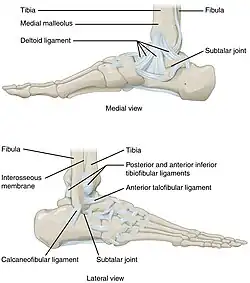

The ankle, the talocrural region[1] or the jumping bone (informal) is the area where the foot and the leg meet.[2] The ankle includes three joints: the ankle joint proper or talocrural joint, the subtalar joint, and the inferior tibiofibular joint.[3][4][5] The movements produced at this joint are dorsiflexion and plantarflexion of the foot. In common usage, the term ankle refers exclusively to the ankle region. In medical terminology, "ankle" (without qualifiers) can refer broadly to the region or specifically to the talocrural joint.[1][6]

The main bones of the ankle region are the talus (in the foot), the tibia, and fibula (both in the leg). The talocrural joint is a synovial hinge joint that connects the distal ends of the tibia and fibula in the lower limb with the proximal end of the talus.[7] The articulation between the tibia and the talus bears more weight than that between the smaller fibula and the talus.

Ankle joint

The talocrural joint is the only mortise and tenon joint in the human body,[9]: 1418 the term likening the skeletal structure to the woodworking joint of the same name. The bony architecture of the ankle consists of three bones: the tibia, the fibula, and the talus. The articular surface of the tibia may be referred to as the plafond (French for "ceiling").[10] The medial malleolus is a bony process extending distally off the medial tibia. The distal-most aspect of the fibula is called the lateral malleolus. Together, the malleoli, along with their supporting ligaments, stabilize the talus underneath the tibia.

Because the motion of the subtalar joint provides a significant contribution to positioning the foot, some authors will describe it as the lower ankle joint, and call the talocrural joint the upper ankle joint.[11] Dorsiflexion and Plantarflexion are the movements that take place in the ankle joint. When the foot is plantar flexed, the ankle joint also allows some movements of side to side gliding, rotation, adduction, and abduction.[12]

The bony arch formed by the tibial plafond and the two malleoli is referred to as the ankle "mortise" (or talar mortise). The mortise is a rectangular socket.[1] The ankle is composed of three joints: the talocrural joint (also called talotibial joint, tibiotalar joint, talar mortise, talar joint), the subtalar joint (also called talocalcaneal), and the Inferior tibiofibular joint.[3][4][5] The joint surface of all bones in the ankle is covered with articular cartilage.

Ligaments

The ankle joint is bound by the strong deltoid ligament and three lateral ligaments: the anterior talofibular ligament, the posterior talofibular ligament, and the calcaneofibular ligament.

- The deltoid ligament supports the medial side of the joint, and is attached at the medial malleolus of the tibia and connect in four places to the talar shelf of the calcaneus, calcaneonavicular ligament, the navicular tuberosity, and to the medial surface of the talus.

- The anterior and posterior talofibular ligaments support the lateral side of the joint from the lateral malleolus of the fibula to the dorsal and ventral ends of the talus.

- The calcaneofibular ligament is attached at the lateral malleolus and to the lateral surface of the calcaneus.